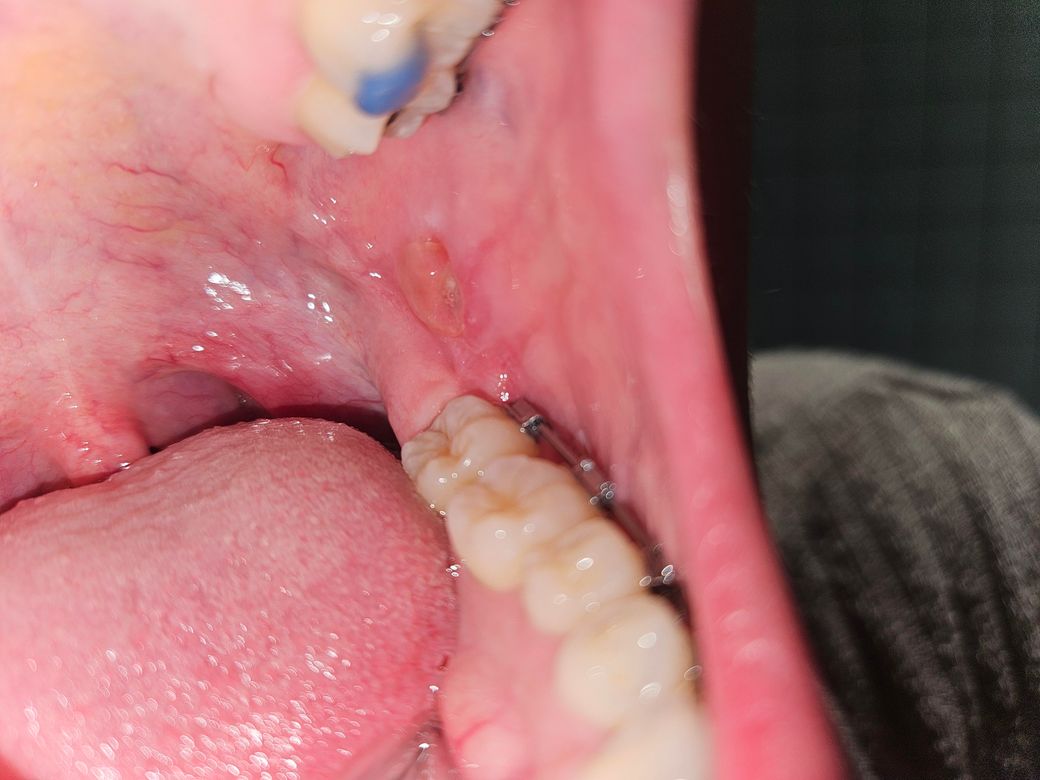

입 안에 구멍이 났는데 구내염인가요?

구내염이 처음 난건 아닌데 너무 크고 좀 깊어서ㅠㅠ 이렇게 아픈 구내염은 처음인데요 이거 구내염 맞나요?ㅠㅠㅠ 너무 아파요 좀 깊기도 한거같아요